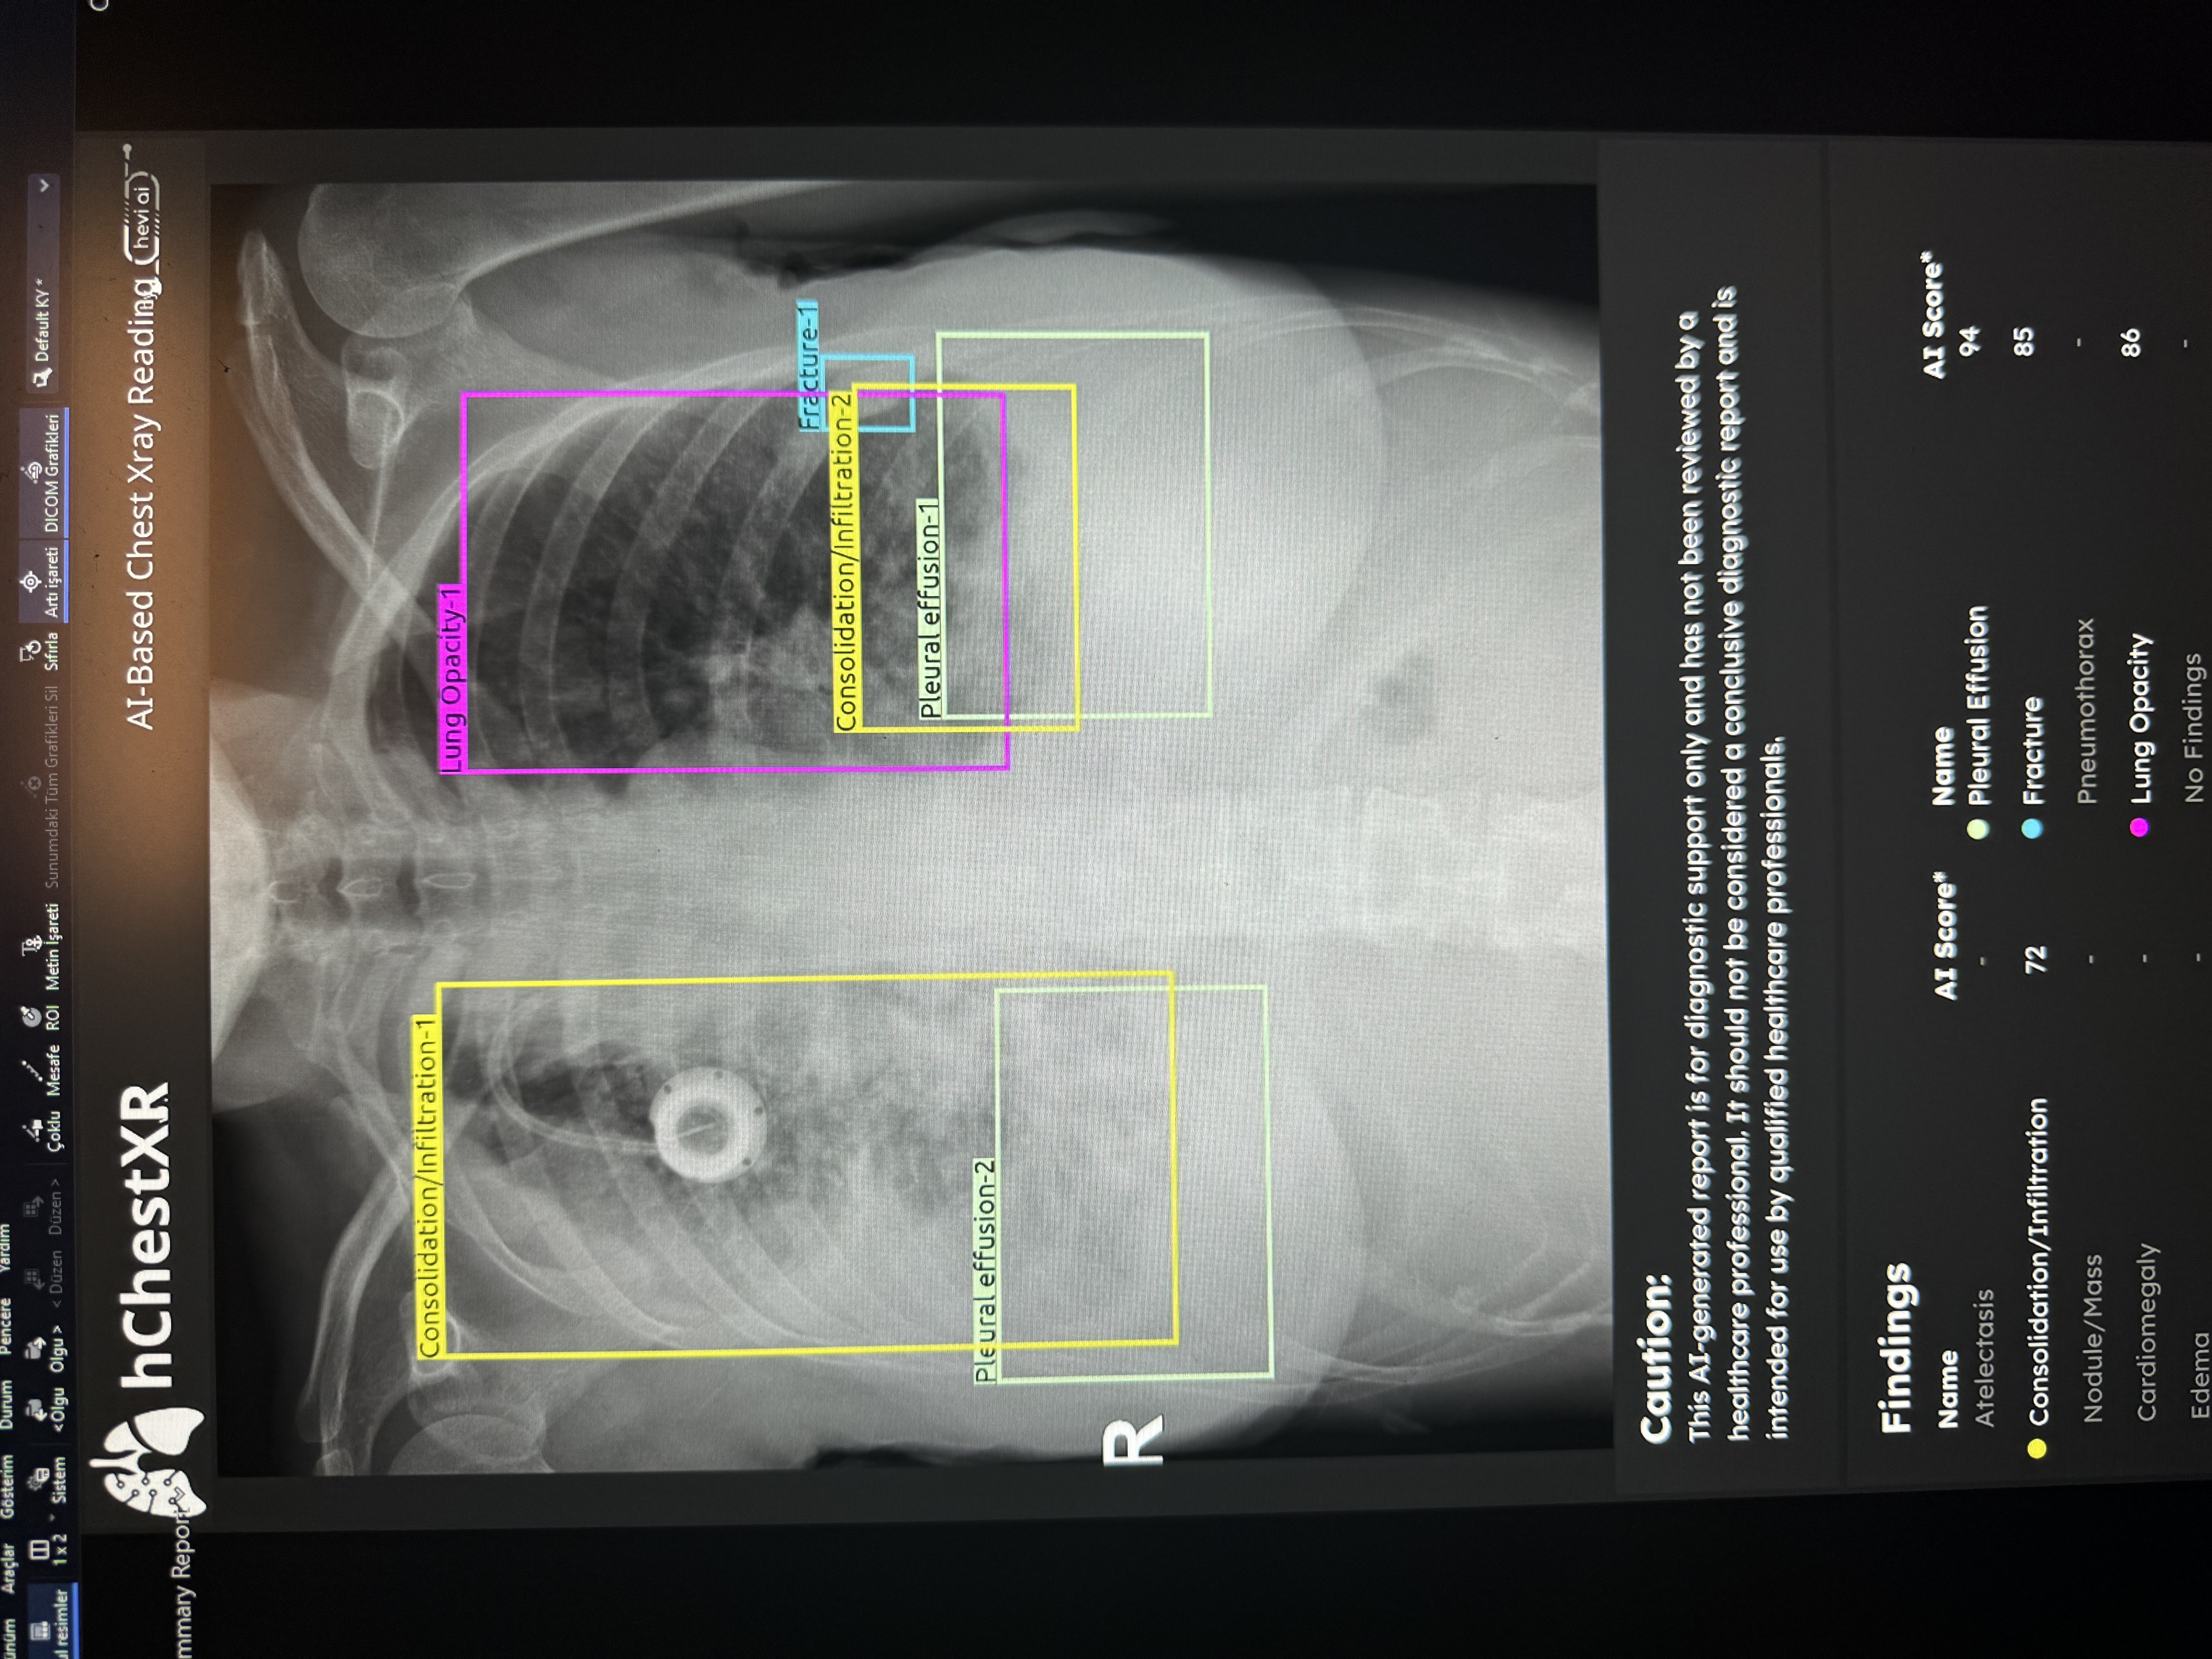

Yapay zeka gelişen teknoloji ile birlikte hayatımızın artık çoğu alanında yer alıyor. Özellikle dijital dünyada, yapay zeka destekli navigasyonlar, sosyal ağlar, chat programları, tıp alanlar gibi yaygın bir şekilde kullanılıyor.